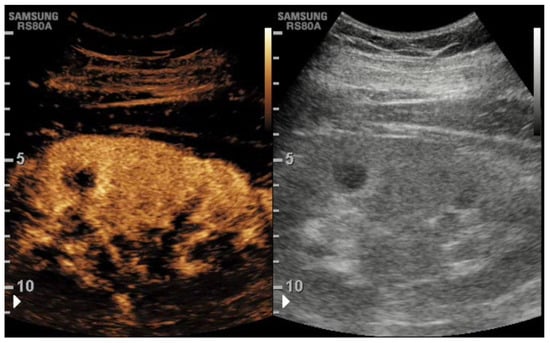

2.4. CEUS

2.5. CEUS Technique